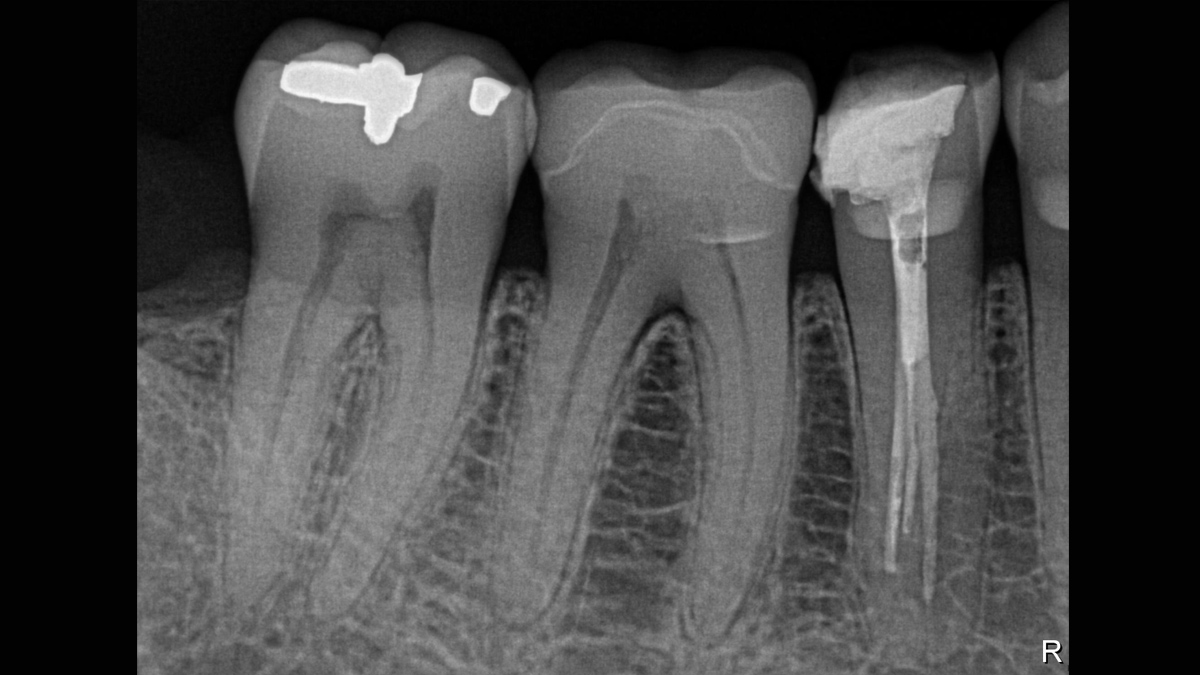

Gallery of Sample Images